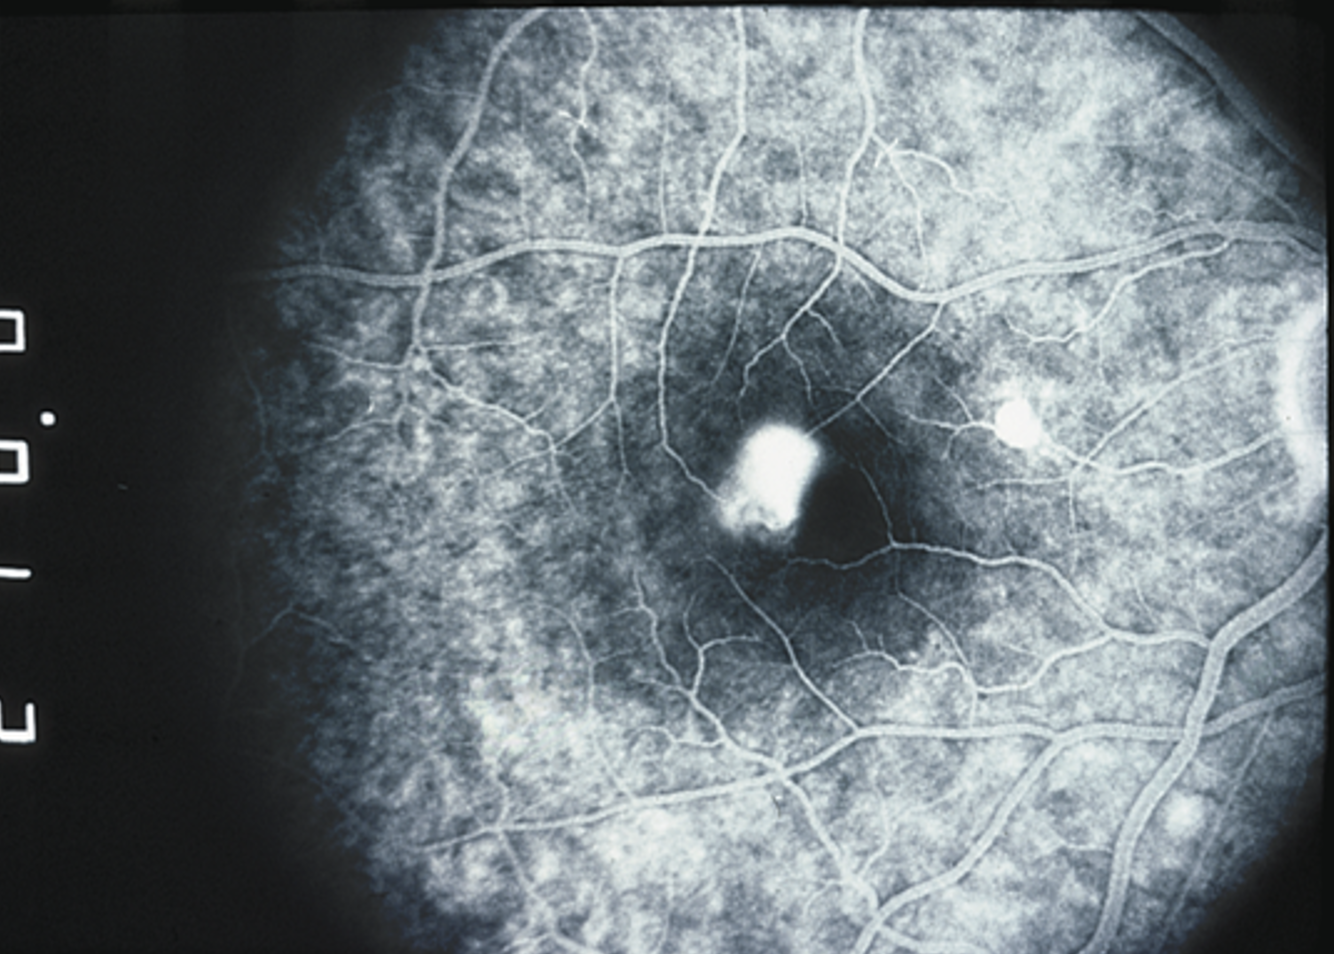

Leaking sub retinal net in the fovea visualized via fluorescein angiography (injected into arm vein)

(trmt: anti-VEGF)